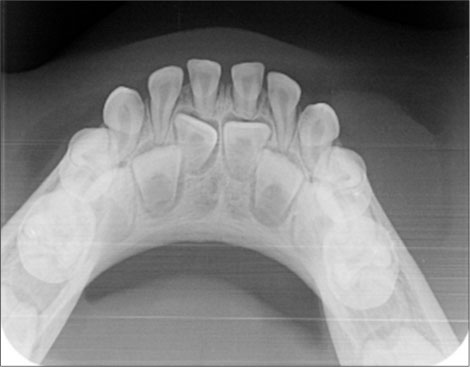

A 4-year-old female patient came with a complaint of growth in the lower back tooth region of lower jaw for 1 week. Parents of the patient noticed the growth a week back which was smaller in size initially which increased suddenly to the present size. Growth was not associated with pain or any other symptoms initially but later developed discomfort while eating associated with mild pain. The patient was given anti-inflammatory medication for the relief of pain and swelling for about 3 days, but there was no reduction in size of the growth. Medical and family histories were noncontributory. On extraoral examination, fullness is seen on the left lower third of face. A solitary left submandibular lymph node enlargement is felt, which is freely movable and tender. Intraorally, an exophytic growth was seen arising from gingiva in relation to 73, 74, and 75 tooth region [Figure 1] measured approximately around size 2 cm × 3 cm, slight pale in color with pinpoint erythematous areas. This appeared to be covered by keratotic surface and seemed to have papillary projections. On palpation, the lesion was pedunculated fibrous inconsistency, nontender, and slight bleeding on provocation, and diascopy test was negative. Considering the patient’s history and clinical examination, a provisional differential diagnosis was arrived which is as follows PG, verrucous hyperplasia, hemangioma, peripheral giant-cell granuloma, peripheral ossifying fibroma, fibroma, and peripheral odontogenic fibroma. The following sets of radiographs were advised to rule out any bony involvement. Intraoral periapical radiograph (IOPA) and occlusal radiographs showed soft-tissue shadow with respect to 73, 74, and 75 [Figure 2] and [3]. Later, complete blood picture was done which did not show any variations from the normal limits. The lesion was subjected for excisional biopsy under local anesthesia [Figure 4] and [5] and subjected to histopathological examination which revealed to be angiomatous granuloma [Figure 6] and [7]. The patient was followed up for 1 year after surgery and there was no evidence of recurrence.

| Figure. 3 Occlusal radiograph showing soft-tissue shadow in relation to 73, 74, and 75